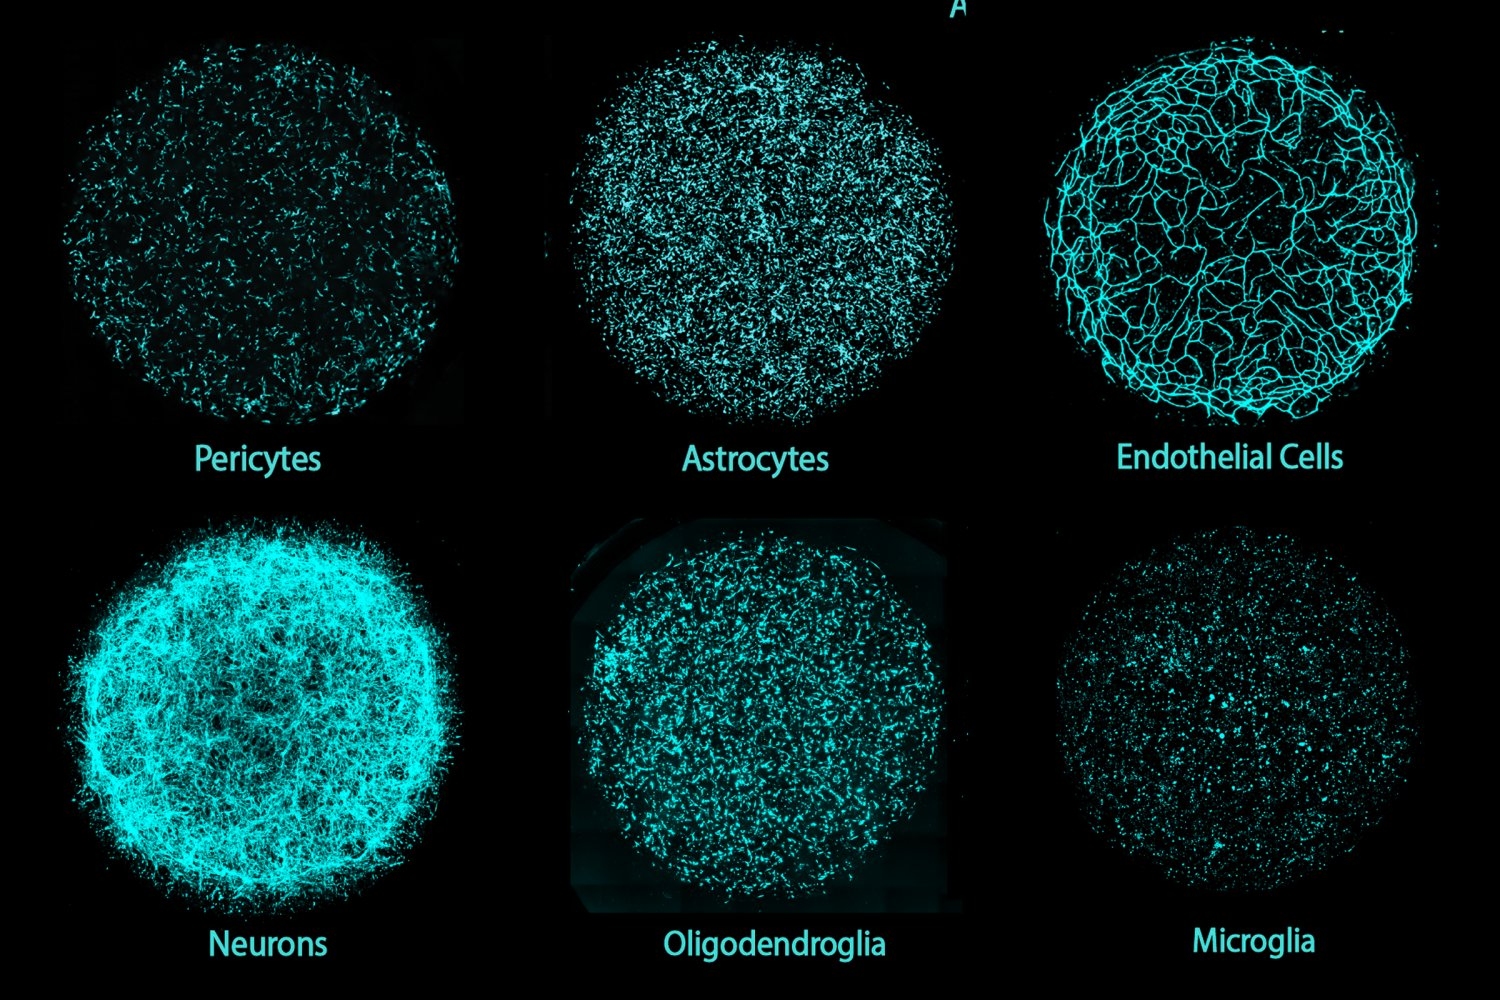

- MIT researchers invent new human brain model to enable disease research, drug discoveryCultured from induced pluripotent stem cells, “miBrains” integrate all major brain cell types and model brain structures, cellular interactions, activity, and pathological features.